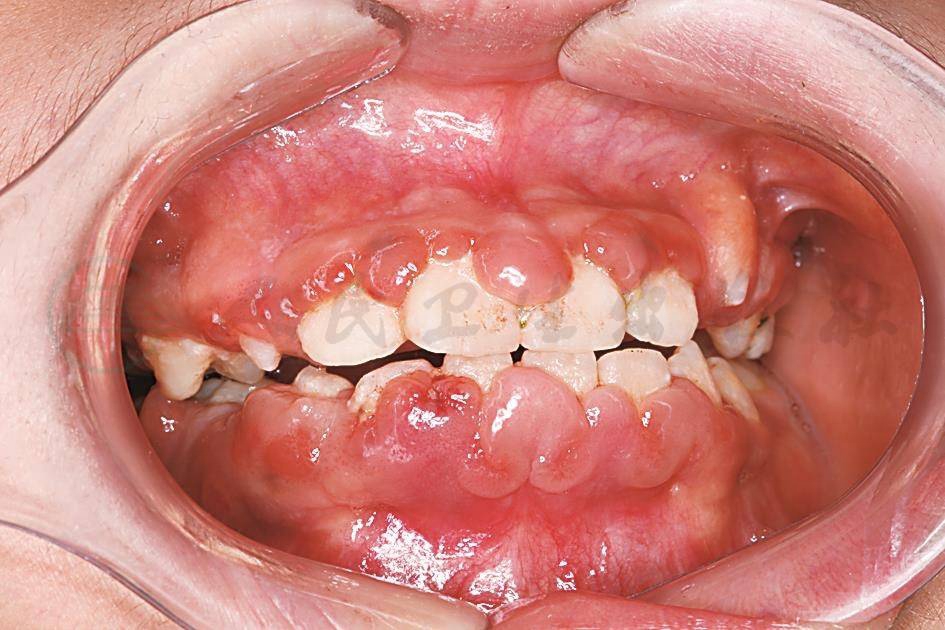

苯妥英钠所致的牙龈肥大一般开始于服药后的1~6个月内,增生肥大起始于唇颊侧或舌腭侧龈乳头,呈小球状突起于牙龈表面,继而肥大的龈乳头继续增大而互相靠近或相连,并向𬌗向(龈缘)扩展,盖住部分牙面,使牙龈外观发生明显的变化(图3)。肥大增生牙龈的表面呈颗粒状或小叶状。近、远中肥大的龈乳头在牙面相接处呈裂沟状。牙龈增生肥大严重时能使牙齿发生移位、扭转,以致牙列不齐。肥大的牙龈组织一般呈淡粉红色,质地坚韧,略有弹性,不易出血,多数患儿无自觉症状,无疼痛。牙龈肥大的好发区域依次为:上颌前牙唇面最好发,其次是下颌前牙唇面、上颌后牙颊面和下颌后牙颊面。牙龈增生肥大的临床表现与服药的年龄阶段有关。在恒牙萌出前开始服用,牙龈组织增生肥大和纤维化会使恒牙萌出受阻。

图3药物性牙龈肥大

患儿,女,10岁,因癫痫服用苯妥英钠3个月后出现牙龈肥大